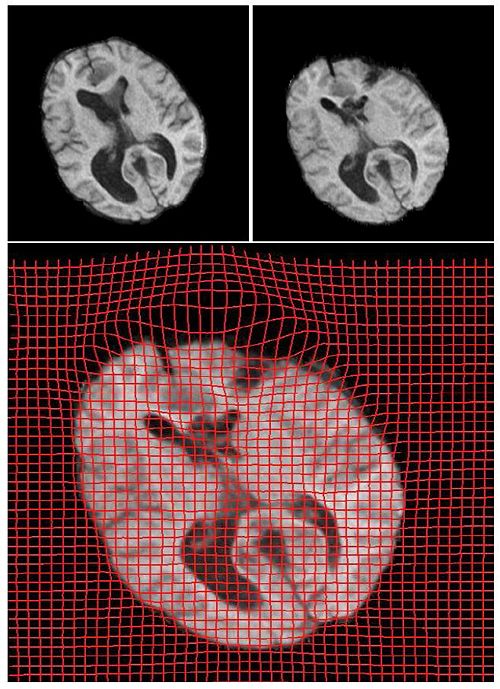

Below we show the results from registration of two 3D brain MRI datasets. The first data set was pre-operative while the second data set was acquired during surgery (craniotomy). Both were resampled to 256*256*256 for uniform voxel size and the skull was removed. We show the results from two axial slices of the 3D brain volumes. The sag and compression areas can easily be seen in the deformed grid shown below. The reults shown are after 3600 iterations, requiring less than 15 minutes of computation time (Dual Xeon 1.6GHz + nVidia GeForce 8800 GX GPU. The optimal computation time was found to occur for a grid size of 128*128*128 where about 1000 iterations execute in less than 15 seconds. This is due to the memory limitations on the graphics card used.

3D Registration Results on axial slices. We visualize the optimal transport map (right) in the form of a vector field corresponding to the directions of deformation between pre-op (left) and post-op (center) brains. Data size 256*256*256.